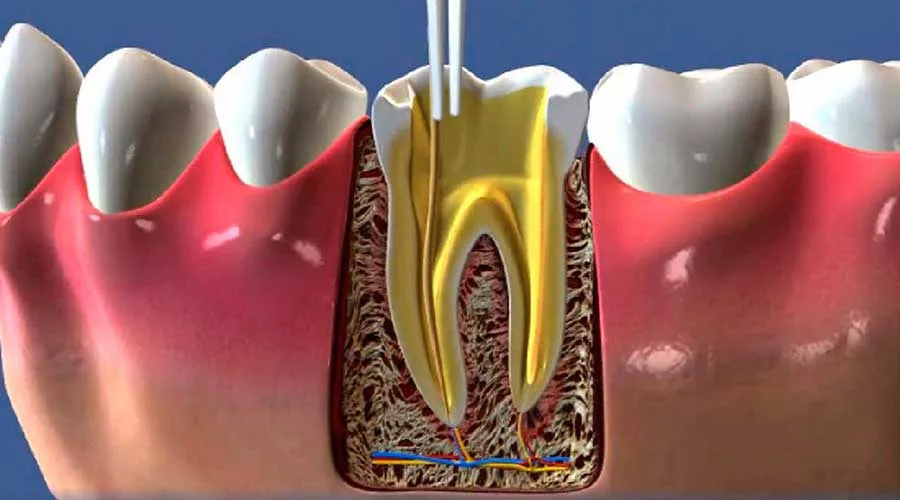

Abordagens Eficazes para o Abscessos Dentários Tratamento

As intervenções para o abscessos dentários tratamento variam conforme a gravidade e a origem da infecção. É essencial contar com auxílio profissional para determinar qual técnica trará o melhor resultado para cada caso.

Existem opções terapêuticas que possibilitam o alívio imediato da dor enquanto eliminam o foco infeccioso. O acompanhamento rigoroso assegura que a recuperação ocorra sem intercorrências.

Procedimentos cirúrgicos: drenagem e suas vantagens

Em situações de maior complexidade, pode ser preciso realizar um procedimento para drenar o conteúdo do abscesso. Essa técnica remove o acúmulo de pus e alivia a pressão interna nos tecidos.

A intervenção oferece um alívio quase imediato da dor pulsante. Além disso, a drenagem facilita a ação de outros medicamentos e acelera o processo de cicatrização.